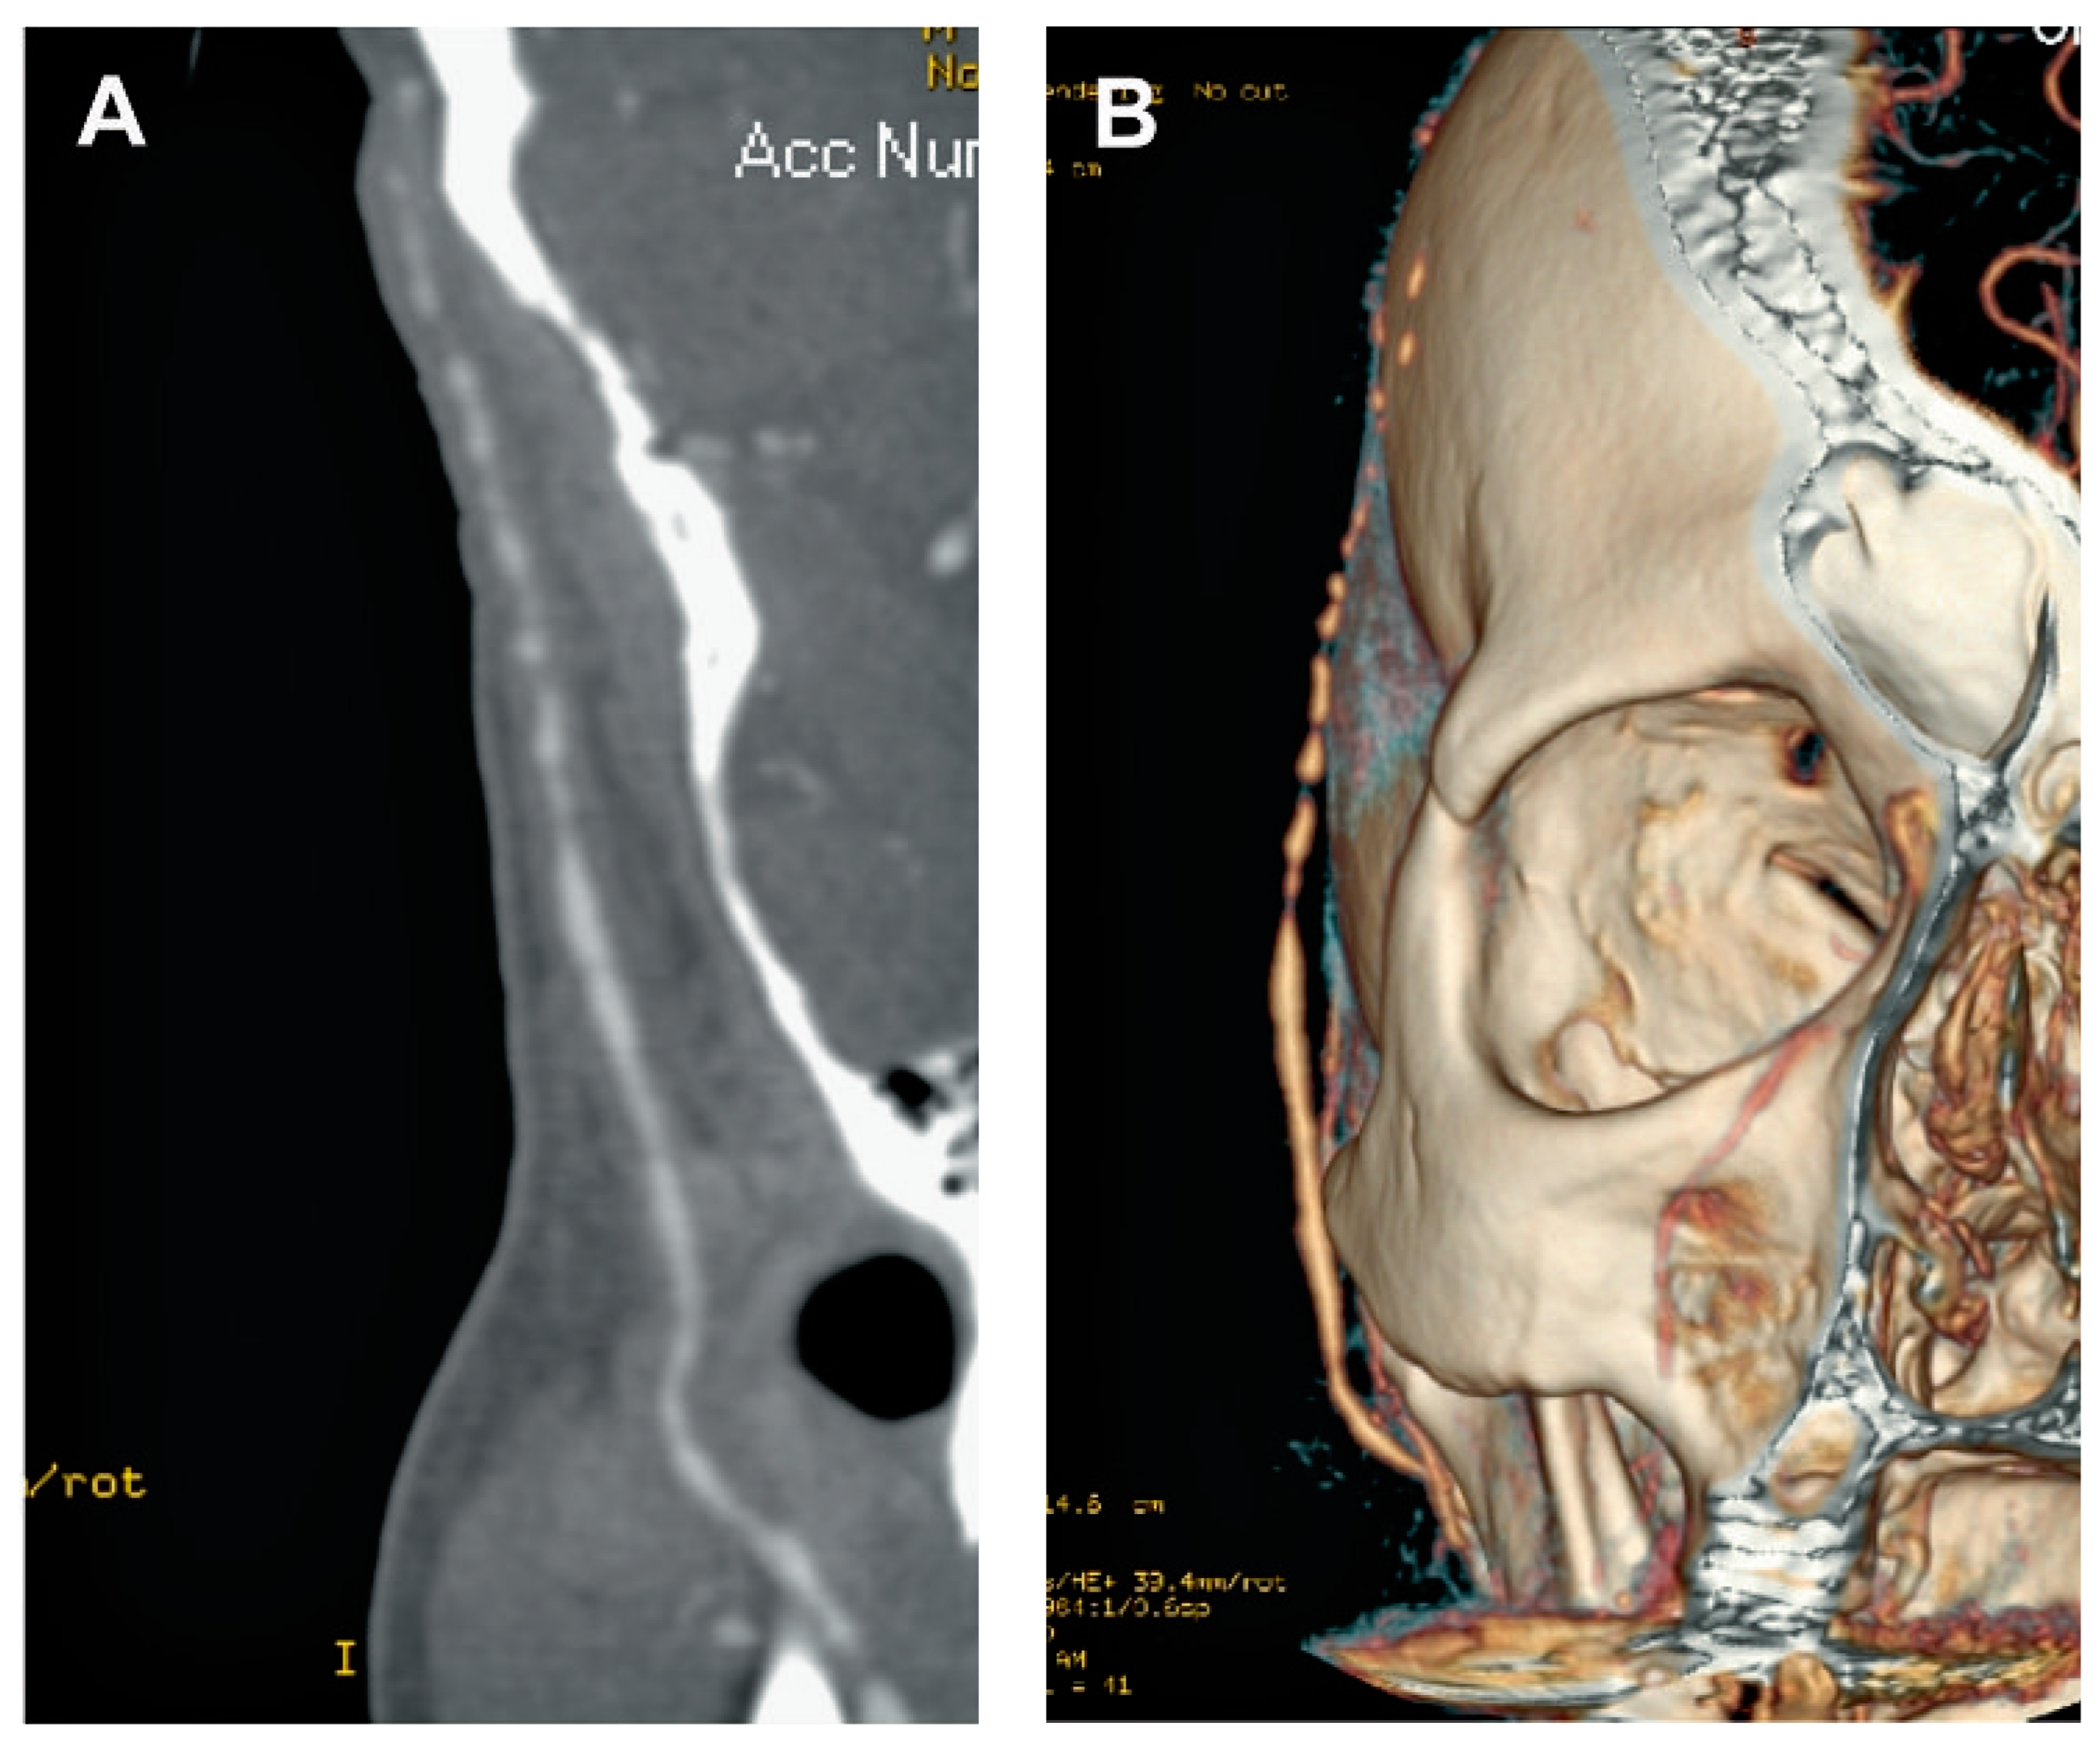

![]() |